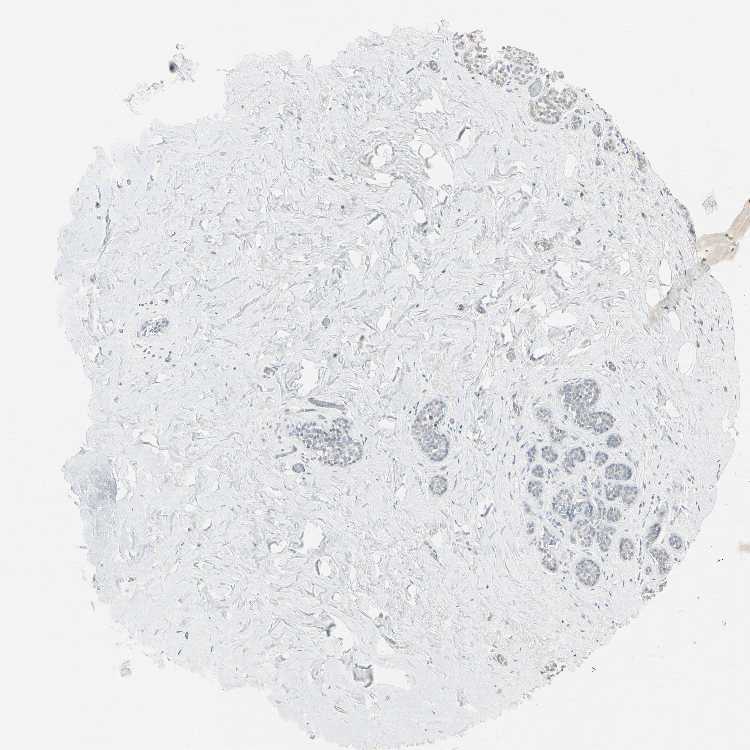

BREAST - Antibody stainingi

Antibody staining in the annotated cell types in the current human tissue is reported as not detected, low, medium, or high, based on conventional immunohistochemistry profiling in selected tissues. This score is based on the combination of the staining intensity and fraction of stained cells.

Each image is clickable and will lead to virtual microscopy that enables deeper exploration of all samples and also displays staining intensity scores, fraction scores and subcellular localization as well as patient and tissue information for each sample.

Antibody HPA007164Antibody HPA008905

Adipocytes Not detectedNot detected

Glandular cells Not detectedNot detected

Myoepithelial cells Not detectedNot detected